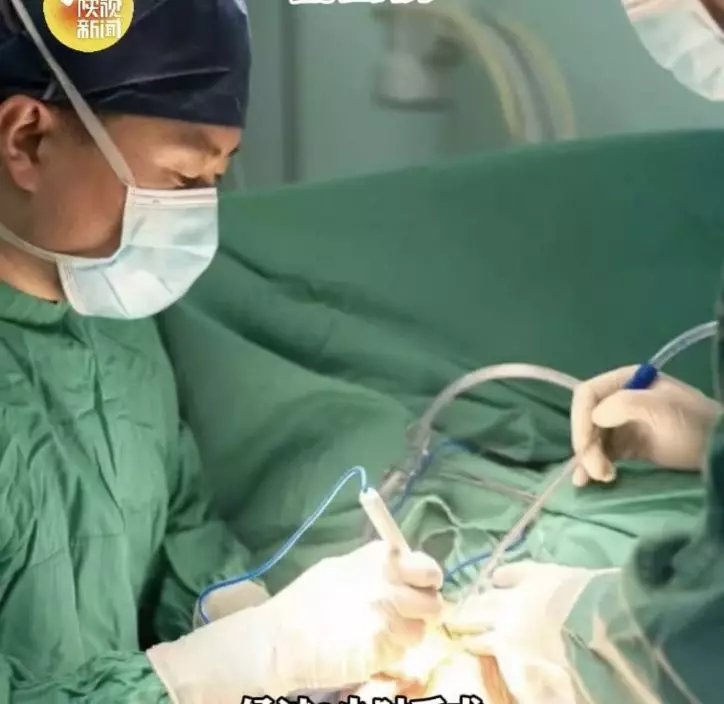

2小時手術完整切除 多年負重終於解除

唐都醫院骨科團隊隨即為馮大爺制定手術方案,經過約2小時手術,醫生成功將這個幾乎包圍上臂四分之三的巨大腫瘤完整切除,並在手術過程中盡量避開重要血管及神經。手術後,馮大爺肩頭多年的負重終於解除,恢復情況良好。

高齡不等於不能手術 術前評估是關鍵

醫生表示,高齡並不代表絕對不能接受手術,關鍵在於術前是否能進行全面評估,以及醫療團隊能否妥善控制手術風險。對於馮大爺而言,若腫瘤繼續增大,不但可能進一步壓迫肩部及上肢組織,也有皮膚破潰、感染等風險,因此手術切除有其必要性。